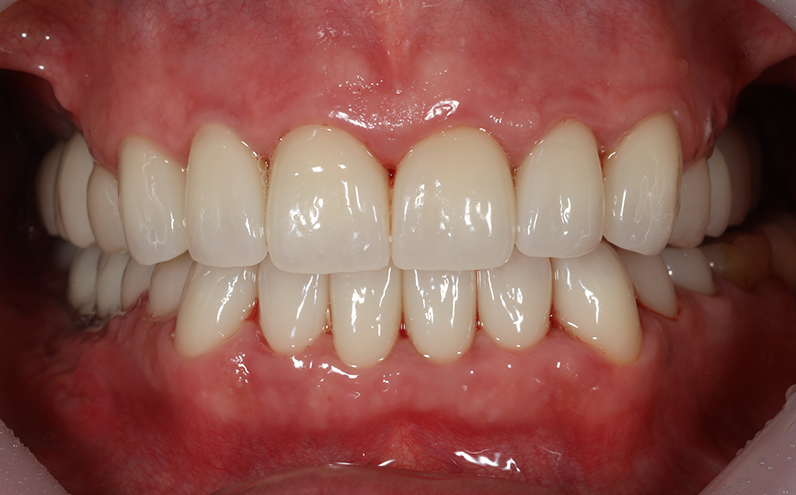

Esthetic prosthetic remake, Dental Implant, Sinus-lifting, Bone Graft

59 y.o, Kazakhstan, Astana

Operating dentist:Roh Hyun Ki